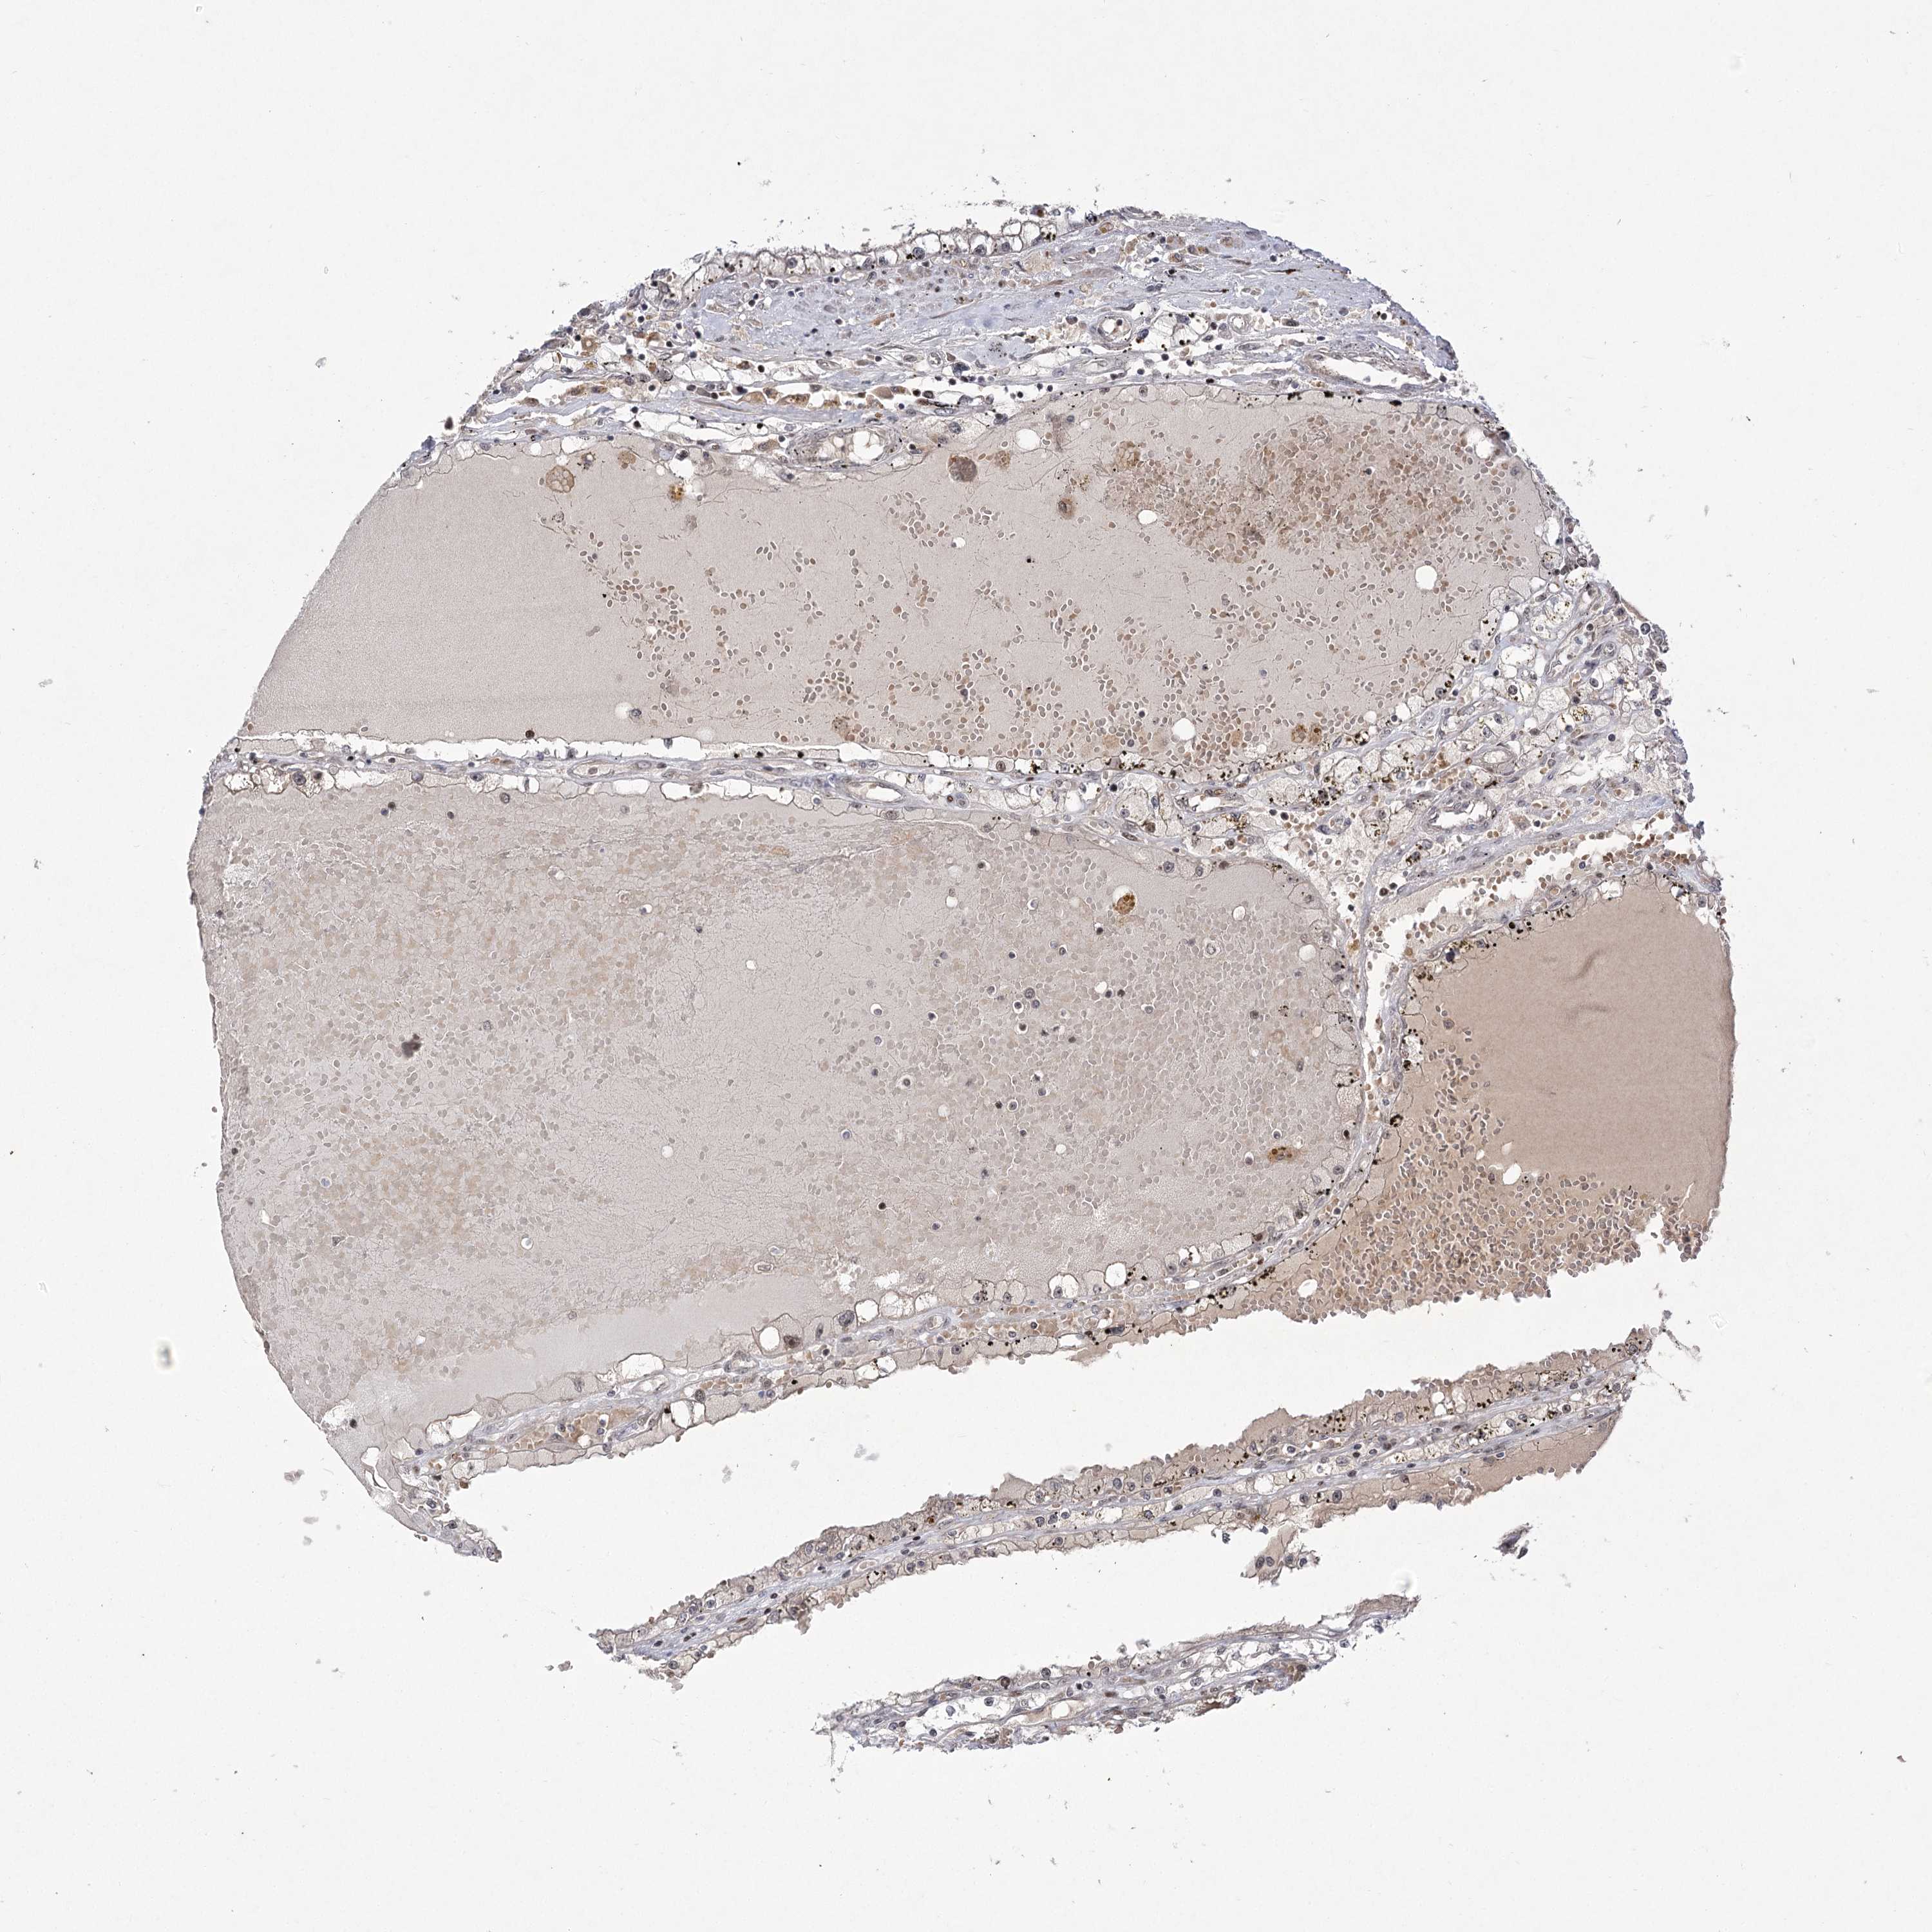

KIDNEY RENAL CLEAR CELL CARCINOMA (VALIDATION) - Interactive survival scatter ploti

The Survival Scatter plot shows the clinical status (i.e. dead or alive) for all individuals in the patient cohort, based on the same data that underlies the corresponding Kaplan-Meier plots. Patients that are alive at last time for follow-up are shown in blue and patients who have died during the study are shown in red.

The x-axis shows the expression levels (FPKM) of the investigated gene in the tumor tissue at the time of diagnosis. The y-axis shows the follow-up time after diagnosis (years). Both axes are complimented with kernel density curves demonstrating the data density over the axes. The top density plot shows the expression levels (FPKM) distribution among dead (red) and alive patients (blue). The right density plot shows the data density of the survived years of dead patients with high and low expression levels respectively, stratified using the cutoff indicated by the vertical dashed line through the Survival Scatter plot. This cutoff is automatically defined based on the FPKM cutoff that minimizes the p-score. The cutoff can be changed by dragging the vertical line or by entering a cutoff value in the square labeled "Current cut-off".

Under the Survival Scatter plot the p-score landscape (black curve; left axis) is shown together with dead median separation (red curve; right axis). Dead median separation is the difference in median mRNA expression between patients who have died with high and low expression, respectively. It is calculated as follows: median FPKM expression of dead patients with high expression - median FPKM expression of dead patients with low expression. This is intended to aid the user in visually exploring custom cutoffs and the associated p-scores and dead median separation.

Individual patient data is displayed and can be filtered by clicking on one or more of the category buttons on the top of the page. Categories describing expression level and patient information include: high, low, alive, dead, female, male and tumor stages. The scale of the x-axis can be toggled between linear and log-scale by clicking on the "x log" button. Mouse-over function shows TCGA ID, patient information and mRNA expression (FPKM) for each patient.

& Survival analysisi

Kaplan-Meier plots summarize results from analysis of correlation between mRNA expression level and patient survival. Patients were divided based on level of expression into one of the two groups "low" (under cut off) or "high" (over cut off). X-axis shows time for survival (years) and y-axis shows the probability of survival, where 1.0 corresponds to 100 percent.

HELQ is not prognostic in Kidney Renal Clear Cell Carcinoma (validation)

Best expression cut offi

: 6.65

Average pTPM 6.4

Number of samples 100